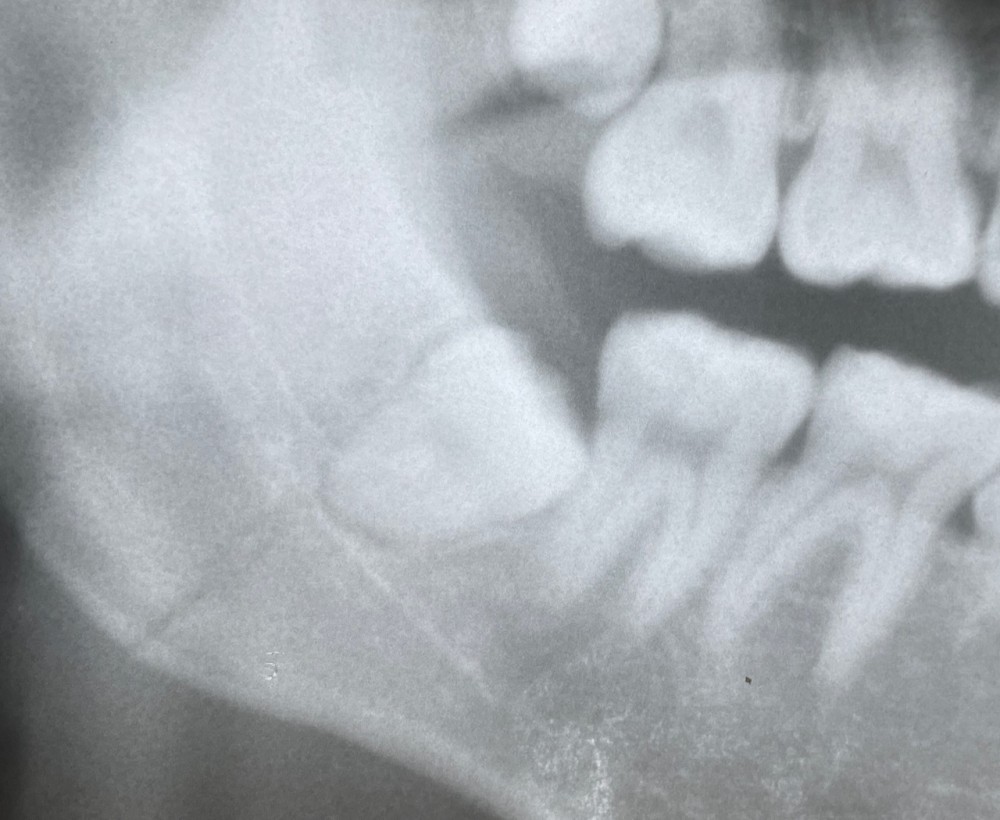

下のエックス線写真は、撮影時20代男性の方のものです。

スポーツ時の外傷で、顎の痛みがあり受診されました。

顎の関節のずれが生じていましたが、骨には異常が見られませんでした。

当日は、脱臼部の整復処置のみで、すぐに回復しました。